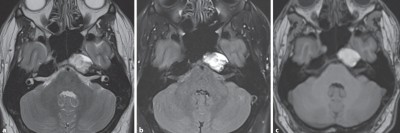

Erektionsstörung: Im Schädel-MRT zeigt sich die Ursache

Ein 26-Jähriger hat seit mehreren Monaten eine verminderte Libido, erektile Dysfunktion sowie reduziertes Ejakulatvolumen. Erste Untersuchungen ergeben einen Testosteronmangel, jedoch keine körperlichen oder neurologischen Beschwerden. Die daraufhin veranlasste Schädel-MRT weist eine Kontrastmittel-Aussparung in der Adenohypophyse auf.

Blutung im transversalen als auch im saggitalen Schnitt/© Instituts für Diagnostische und Interventionelle Radiologie der Uniklinik Köln; mit freundlicher Genehmigung, MRT des Beckens: Uterus und Ovarialtumoren/© Hosten AK et al. / all rights reserved Springer Medizin Verlag GmbH, Spinale Stenose/© A. Frank, Cholesterolgranulom im MRT/© Frederik F/ all rights reserved Springer Medizin Verlag GmbH, Ultraschalluntersuchung der Schilddrüse/© Olesia Bilkei / Fotolia (Symbolbild mit Fotomodellen), Hirntumoren sichtbar im MRT/© semnic / Getty Images / iStock (Symbolbild mit Fotomodell), Subdurales Hämatom im MRT-Befund/© Springer Medizin, Magnetresonanztomographie/© Svitlana / Stock.adobe.com (Symbolbild mit Fotomodell), Springer Medizin Podcast - Trigeminusneuralgie/© (M) pain au chocolat / stock.adobe.com (Symbolbild mit Fotomodell), Tumor im linken Kleinhirnbrückenwinkel und inneren Gehörgang (linkes Bild) und Tumor am Foramen jugulare (rechtes Bild)/© Springer Medizin, Ischämischer Insult/© stockdevil / iStock / Thinkstock, Schreiendes Baby/© AzmanL / Getty Images / iStock (Symbolbild mit Fotomodell), Arzt und Ärztin sehen sich Befunde einer kranialen MRT-Untersuchung an/© Atthapon / stock.adobe.com (Symbolbild mit Fotomodellen), Abklärung von Rückenschmerz bei älterer Patientin/© andreswd / Getty Images / iStock (Symbolbild mit Fotomodellen), Manuelle Behandlung unterer Rückenschmerzen/© Viorika / Getty Images / iStock (Symbolbild mit Fotomodellen), Akute Deckplattenimpressionsfraktur des LWK 2/© Klinikum Bayreuth, Lumbale Spinalkanalstenose/© Birkenmaier C & Fuetsch M / all rights reserved Springer Medizin Verlag GmbH, Verminderte Schulterhebung beim Patient/© Hülsmann Y et al. / all rights reserved Springer Medizin Verlag GmbH, Prolaktinom mit sekundärem hypogonadotropem Hypogonadismus/© Linse K, Hartmann M / all rights reserved Springer Medizin Verlag GmbH, Frau bei Strahlentherapie/© (M) Mark Kostich / Stock.adobe.com (Symbolbild mit Fotomodellen), Neuroradiologe und Assistentin/© (M) tunedin / Stock.adobe.com (Symbolbild mit Fotomodellen), Search Icon, Knochensäge im Einsatz bei Knie-TEP/© Issara / stock.adobe.com (Symbolbild mit Fotomodellen), Lungentrainer/© S@photo / stock.adobe.com (Symbolbild mit Fotomodell), Junge Ärztin vor einem Triage-Zelt/© Milos / Stock.adobe.com (Symbolbild mit Fotomodell)